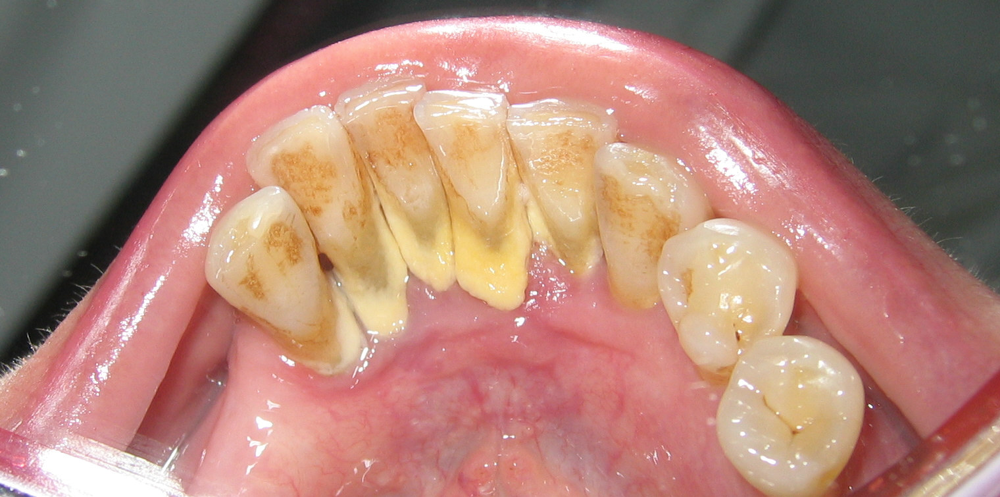

diş taşı nasıl gözükür

Yeterince temizlenmeyen dişlerin üzerindeki sarı-kahverengi diş taşı birikimini gösteren bir örnek. Bu sert tabaka normal fırçalama ile uzaklaştırılamaz ve ancak profesyonel temizleme ile çıkarılabilir.

Diş taşları genellikle diş eti çizgisi boyunca ve ulaşılması zor bölgelerde oluşur. Özellikle alt ön dişlerin arka yüzeylerinde ve üst azı dişlerinin yanağa bakan kısımlarında birikme eğilimindedirler. Bunun nedeni, bu bölgelerdeki tükürük bezlerinin kalsiyum ve fosfat gibi mineraller bakımından zengin salgı yapması ve plağın burada daha kolay sertleşmesidir. Zamanla diş taşı tabakasının yüzeyi pürüzlü bir hal alır ve bu pürüzler yeni bakterilerin tutunmasına elverişli zemin hazırlar. Bu bir kısır döngü oluşturur: daha fazla tartar, daha fazla bakteri plağı birikimi ve daha fazla iltihap anlamına gelir. Bu nedenle diş taşı, sadece diş yüzeyinde kalan bir leke değil, aynı zamanda ağız içi enfeksiyonların temel kaynaklarından biri olarak kabul edilir.